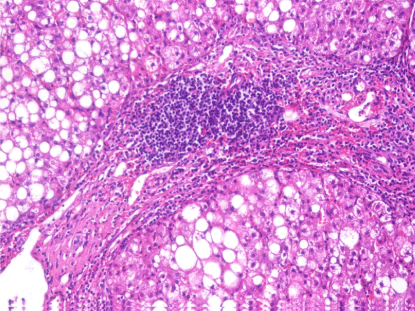

Figure 5. A case of steatohepatitis, merging into cirrhosis (H&E stain,X200)